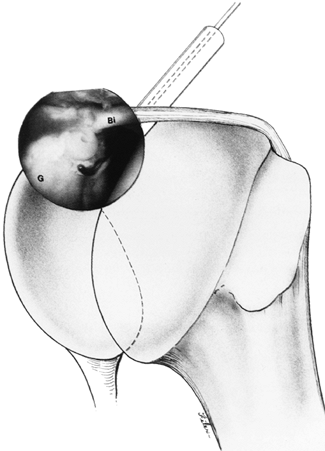

Figure 80.44. Arthroscopic view of a type II SLAP lesion. An anterosuperior portal allows manipulation of the biceps (Bi) and preparation of the glenoid (G),

while the lateral portal allows placement of the guidewire and drill.

(From Warner JJ, Kann S, Marks P. Arthroscopic Repair of Combined

Bankart and Superior Labral Detachment Anterior and Posterior Lesions:

Technique and Preliminary Results. Arthroscopy 1994;10:383, with permission.) -